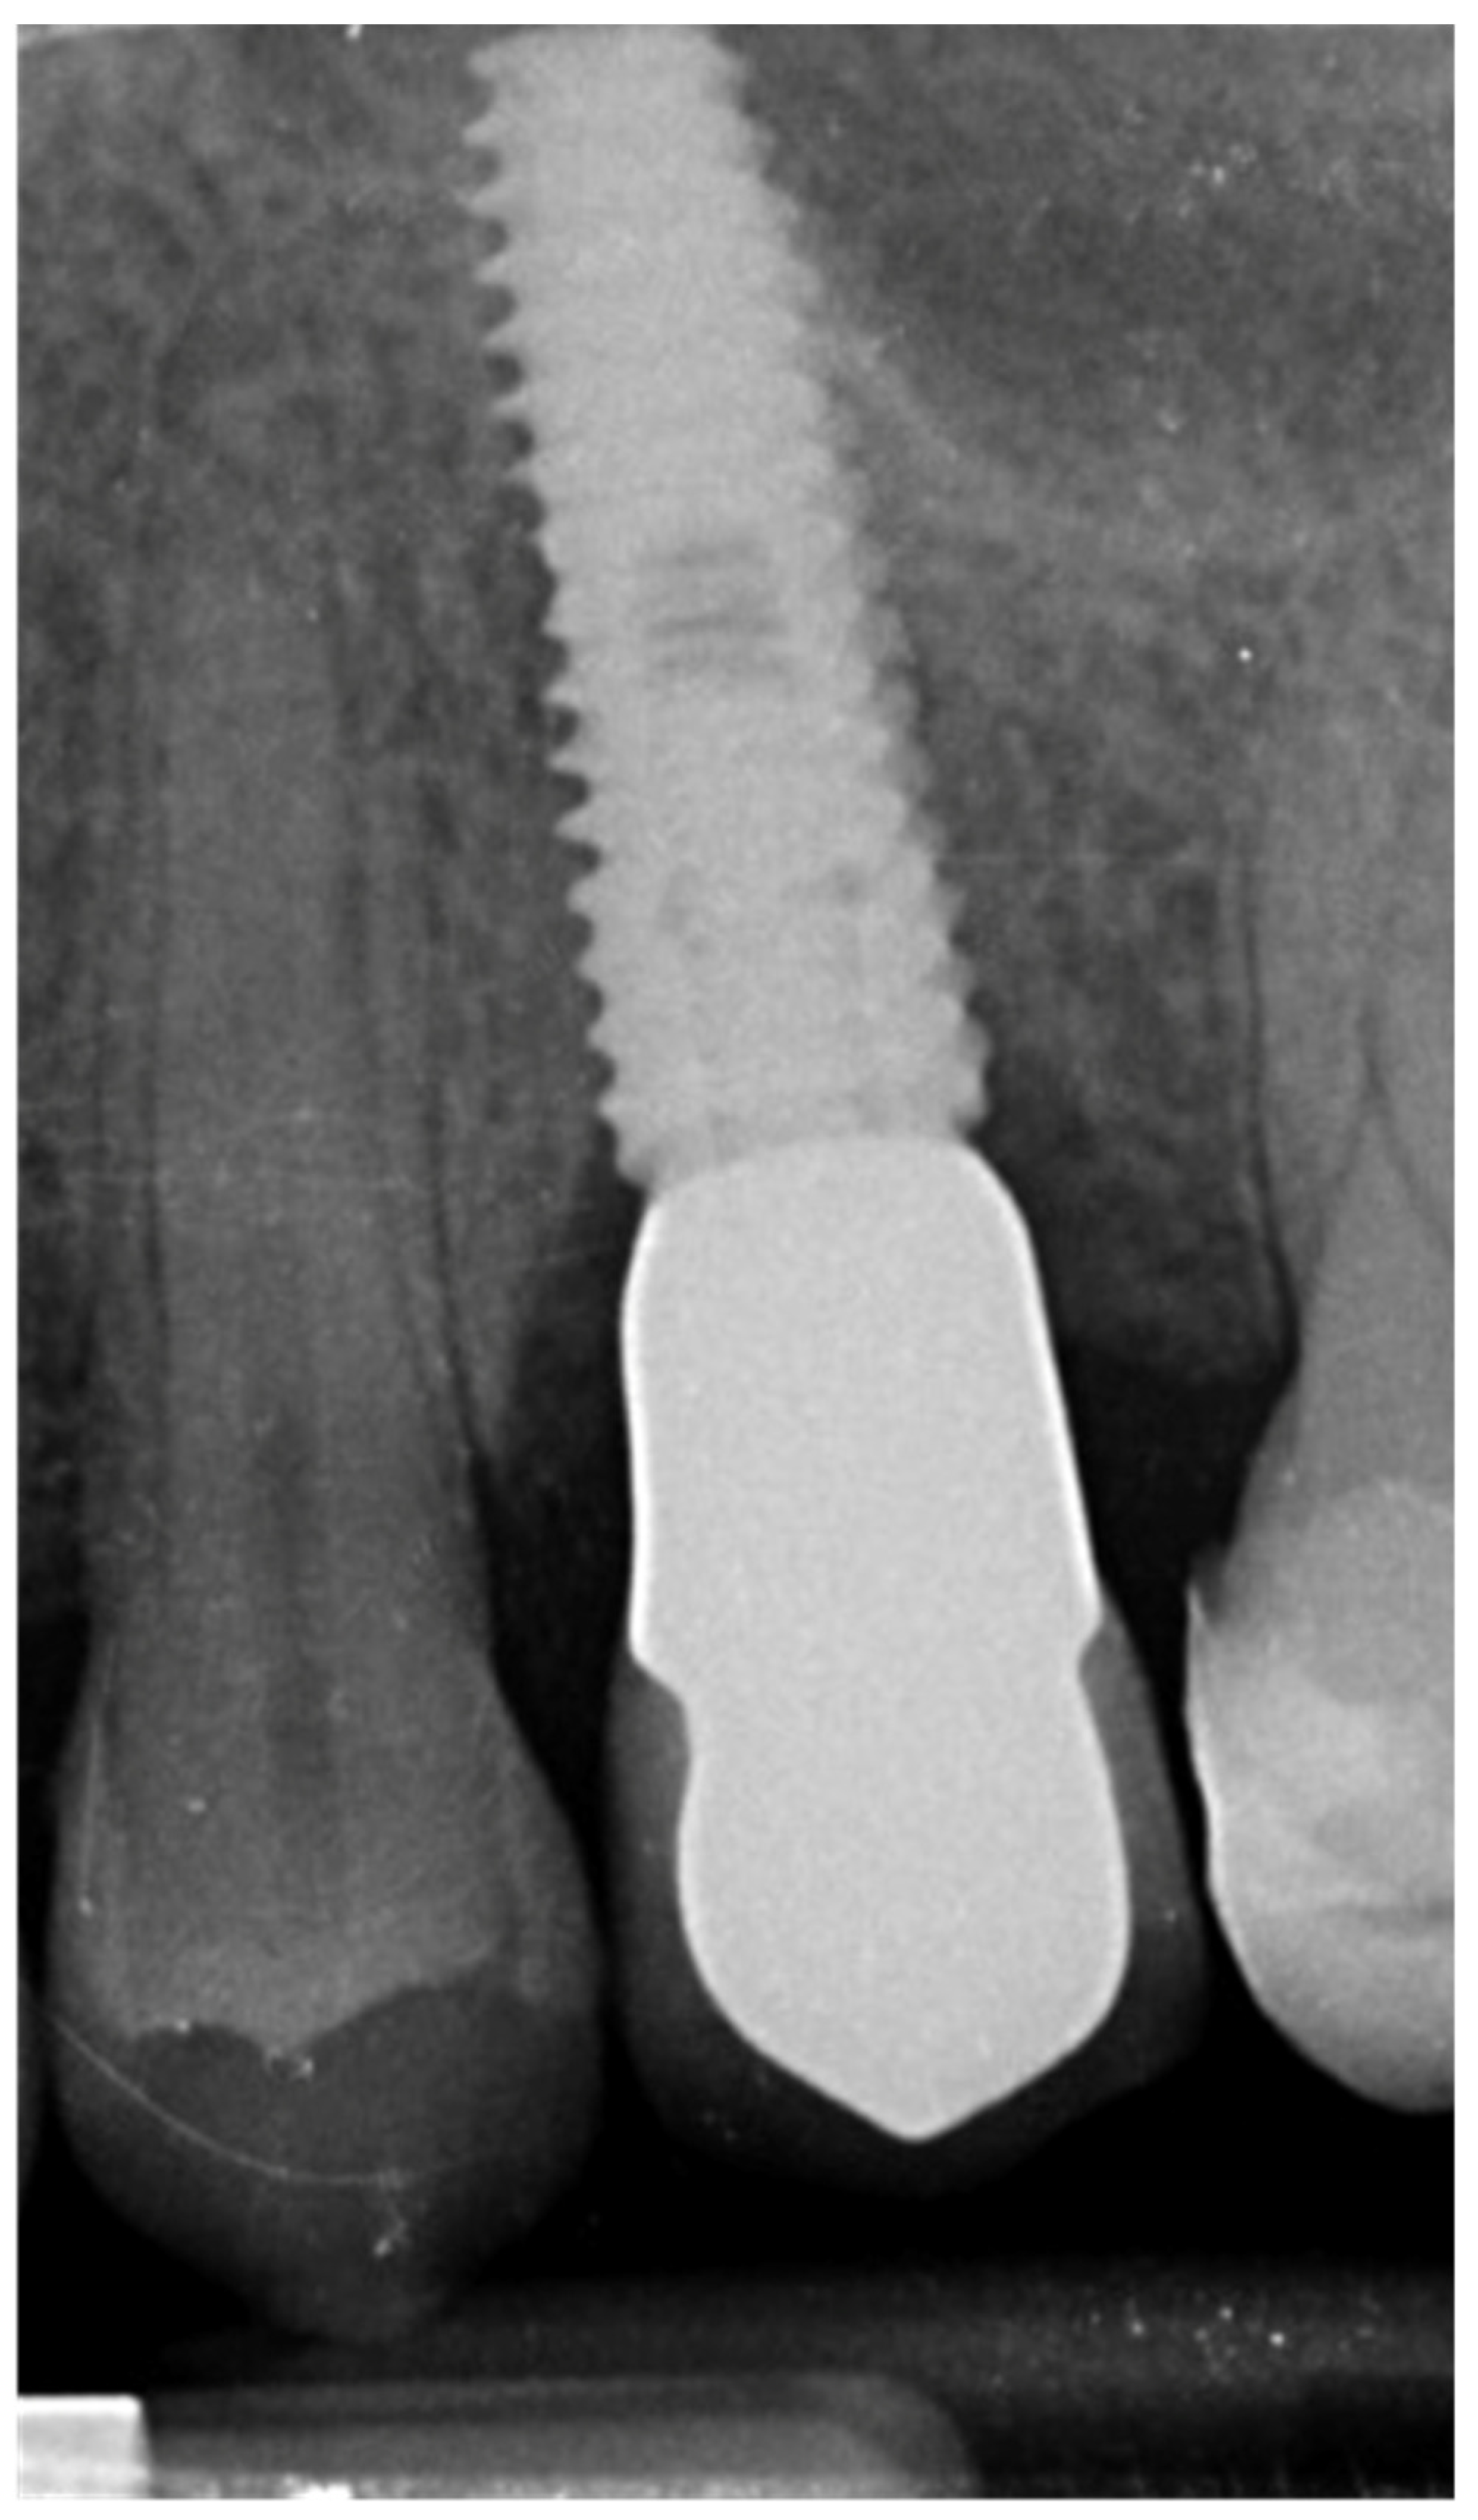

2. Results

2.1. Incidence of Implants Fracture

2.2. Risk Factors for Implants Fracture